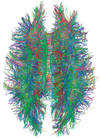

MRI diffusion tensor imaging of white matter tracts

MRI is the investigative tool of choice for neurological cancers over CT, as it offers better visualization of the posterior cranial fossa, containing the brainstem and the cerebellum. The contrast provided between grey and white matter makes MRI the best choice for many conditions of the central nervous system, including demyelinating diseases, dementia, cerebrovascular disease, infectious diseases, Alzheimer's disease and epilepsy.[30][31][32] Since many images are taken milliseconds apart, it shows how the brain responds to different stimuli, enabling researchers to study both the functional and structural brain abnormalities in psychological disorders.[33] MRI also is used in guided stereotactic surgery and radiosurgery for treatment of intracranial tumors, arteriovenous malformations, and other surgically treatable conditions using a device known as the N-localizer.[34][35][36] New tools that implement artificial intelligence in healthcare have demonstrated higher image quality and morphometric analysis in neuroimaging with the application of a denoising system.[37]

| Diffusion tensor |

DTI |

Mainly tractography (pictured) by an overall greater Brownian motion of water molecules in the directions of nerve fibers.[80]